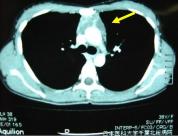

(1)胸壁浸潤肺癌の術前・術後の胸部単純X線および術中写真です。手術は右肺上葉切除術+胸壁合併切除(右第2~6肋骨切除)+縦隔リンパ節郭清を施行しました(下図)。

術前 胸部XP

術後 胸部XP